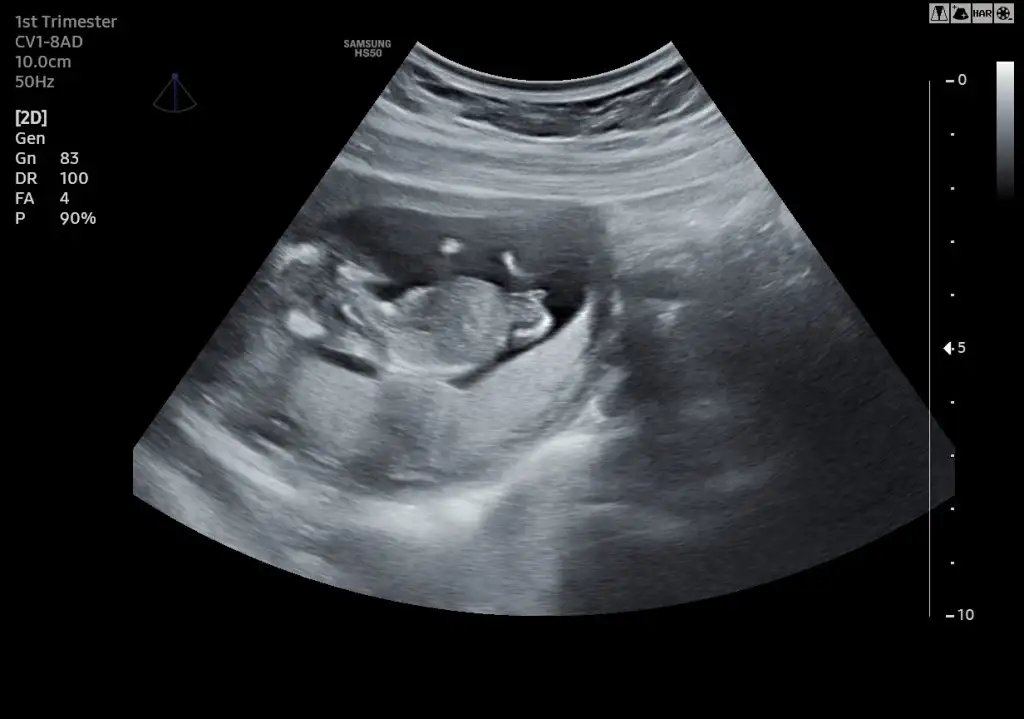

Ya kuzu evet isim yazıyor ya üste ama kırptım bak atıyorumUltrason da isim mi yaziyor

Ahhh tipini seveyim maşallah tam bir bebekYa kuzu evet isim yazıyor ya üste ama kırptım bak atıyorum

Burnunu ıssırabilirmiyimYa kuzu evet isim yazıyor ya üste ama kırptım bak atıyorum

Ya kuzu evet isim yazıyor ya üste ama kırptım bak atıyorum

Ay burna bak minnossYa kuzu evet isim yazıyor ya üste ama kırptım bak atıyorum

Öyle bakıp duruyorum usg fotoğraflarına.